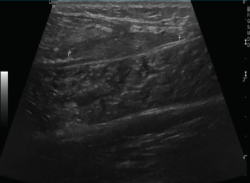

2.2. Roturas

Se observan áreas hipoecoicas de solución de continuidad de las fibras tendinosas(7), con retracción de los márgenes con la contracción muscular cuando la rotura tendinosa es completa (Figuras 9 y 10).

Figura 9. Corte sagital de una ecografía de rodilla: foco hipoecoico por rotura parcial del tendón cuadricipital.

Figura 10. Corte sagital de una ecografía de rodilla: ausencia del tendón rotuliano por rotura completa, con hematoma señalado en el trayecto del tendón.